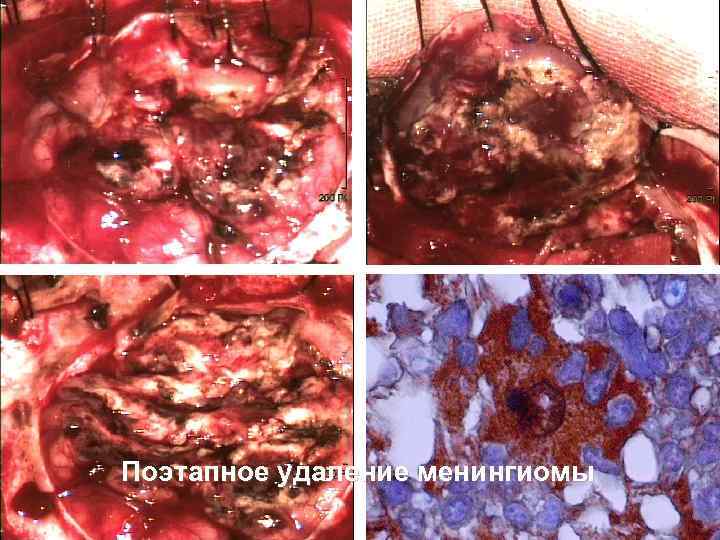

Поэтапное удаление менингиомы 55